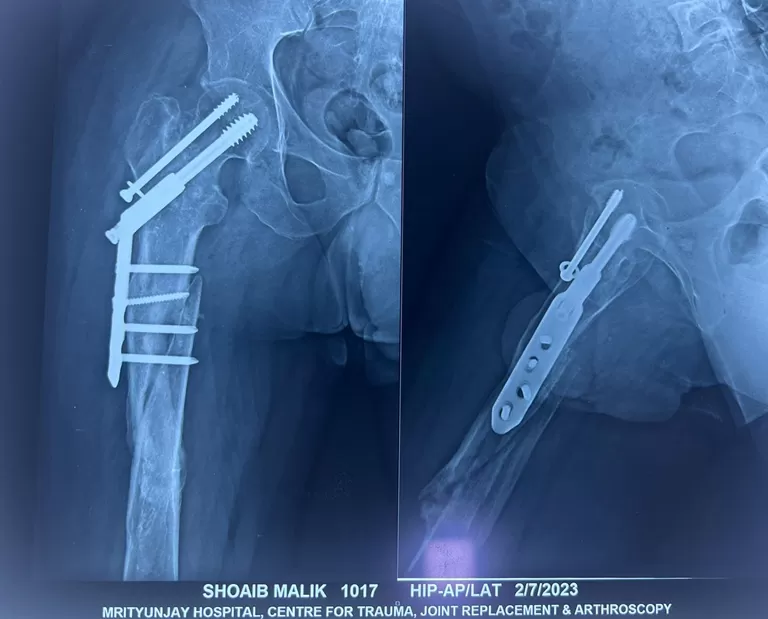

Mr. Shoaib

Name: Mr. Shoaib

Date of Operation: 7 July 2023

Age: 25 Years